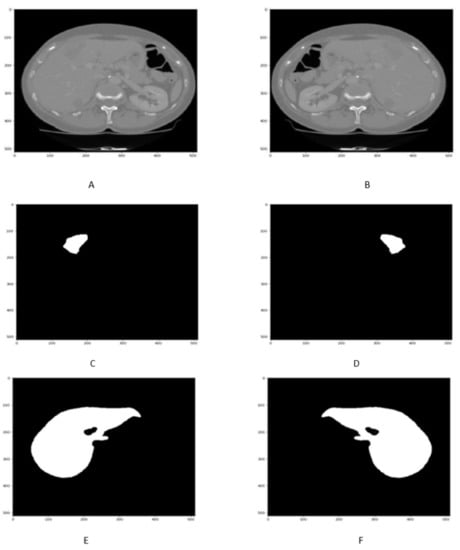

4.2. Liver Segmentation Results

The qualitative and quantitative result of liver CT scan segmentation is shown in Figure 7 and in Table 2. The proposed technique has been obtained regarding liver segmentation as assessed by DSC, accuracy, precision, specificity VOE, and RVD values. The Figure 7A,B and Table 2 highlight the better performance of proposed approach.

Figure 7.

Figure shows that the samples of Liver segmentation in (A,B).